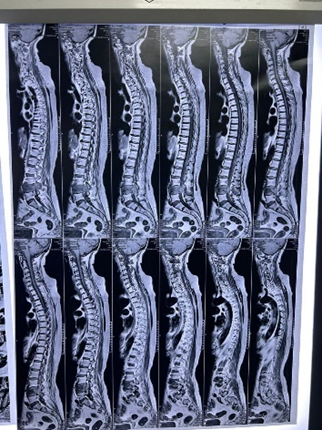

Postpartum Haemorrhage: A Case Series Highlighting Diverse Clinical Profiles and Evolving Management Strategies in a Tertiary Care Setting